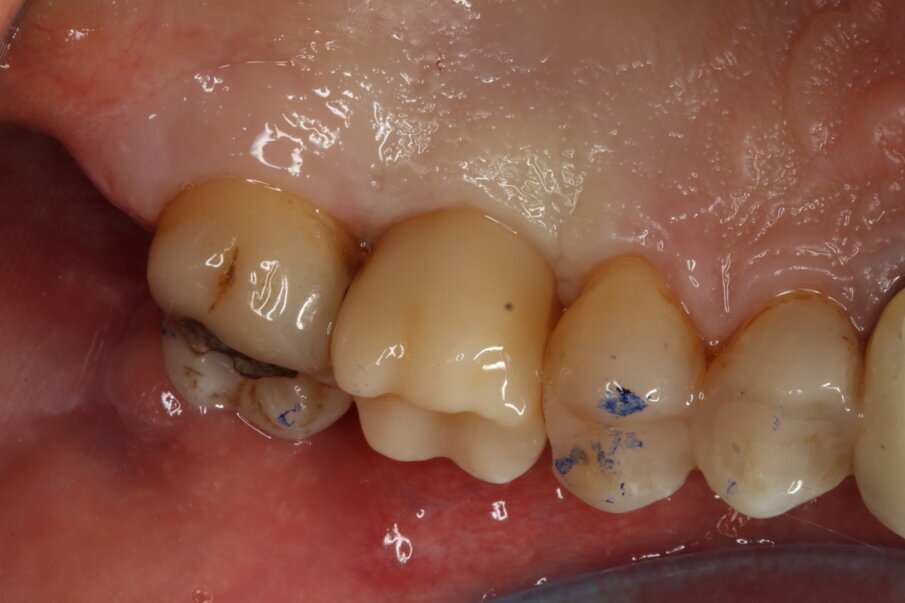

Le radiografie a tre mesi hanno evidenziato un buon rimaneggiamento del biomateriale e segni di neoformazione ossea dal pavimento del seno, confermando le proprietà osteogeniche di OsteoBiol Putty. A sei mesi, l’osso innestato risultava completamente rigenerato, permettendo la finalizzazione protesica con una corona in disilicato di litio cementata su cappa in titanio (Figg. 6-13).

Fig. 10_Corona in disilicato di litio.

Fig. 12_Risultato clinico finale (versante vestibolare).